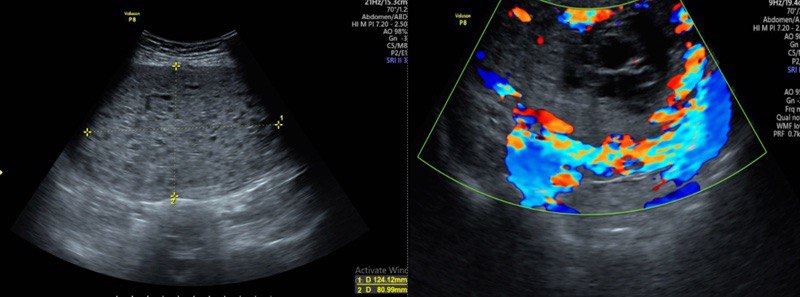

Kết quả, siêu âm cho thấy, vùng hạ vị xuất hiện khối cấu trúc hỗn hợp âm, kích thước khoảng 124 x 81mm, kèm tăng sinh mạch rõ trên siêu âm Doppler. Chụp cắt lớp vi tính (CT Scanner) ghi nhận tử cung kích thước lớn nhưng không thấy hình ảnh túi thai; bên trong là các vùng giảm tỷ trọng dạng dịch xen kẽ mô mềm, tạo hình ảnh đặc trưng dạng “bọt xà phòng”, kèm tăng sinh mạch mạnh quanh tử cung sau tiêm thuốc cản quang. Đặc biệt, nồng độ beta-hCG của bệnh nhân tăng rất cao, lên tới 2.692.965 mIU/mL.

Siêu âm thấy vùng hạ vị của bệnh nhân xuất hiện khối cấu trúc hỗn hợp âm, kèm tăng sinh mạch rõ trên siêu âm Doppler